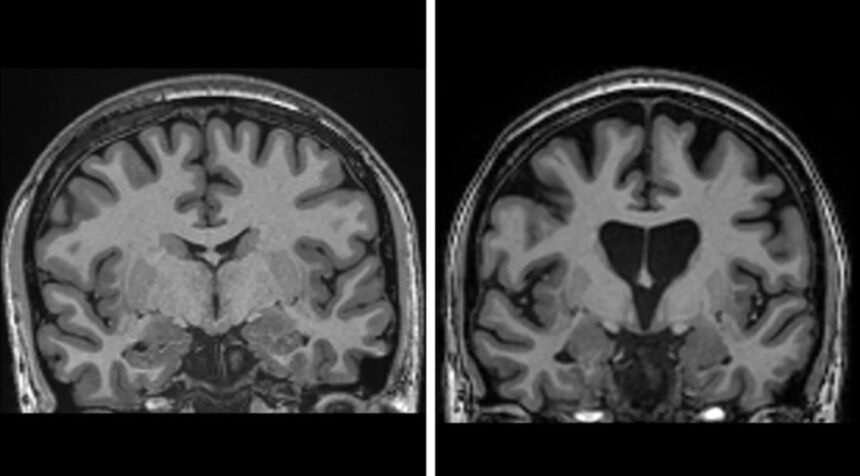

Резултатите од испитувањето, во кое беа вклучени 29 пациенти во Велика Британија и САД, беа објавени од uniQure. Три години по третманот, пациентите кои ја примиле високата доза на лекот покажале просечно 75 проценти побавно напредување на болеста, мерено со тестови за моторна функција, когниција и способност за извршување дневни активности. Наодите, исто така, покажаа значително пониски нивоа на неврофиламенти, маркер за клеточна смрт, што укажува на заштита на невроните.